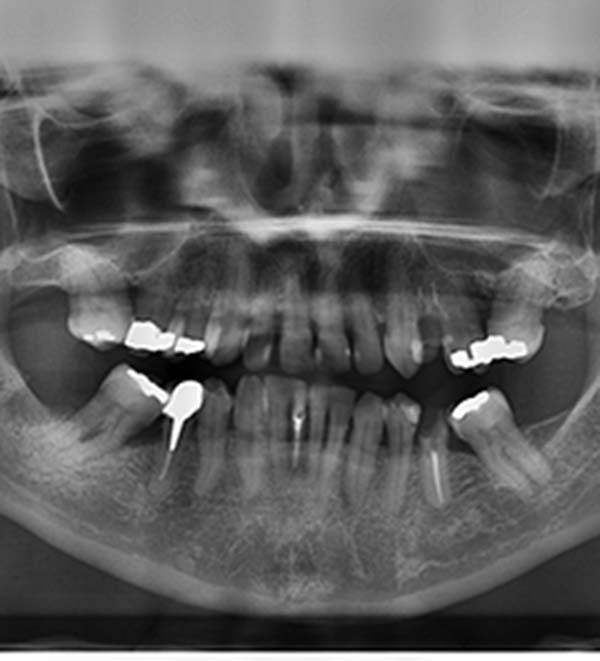

Oral Surgery

We offer a wide range of surgeries. Whether you need a wisdom tooth removed or help dealing with a nasty cavity, our team can help.